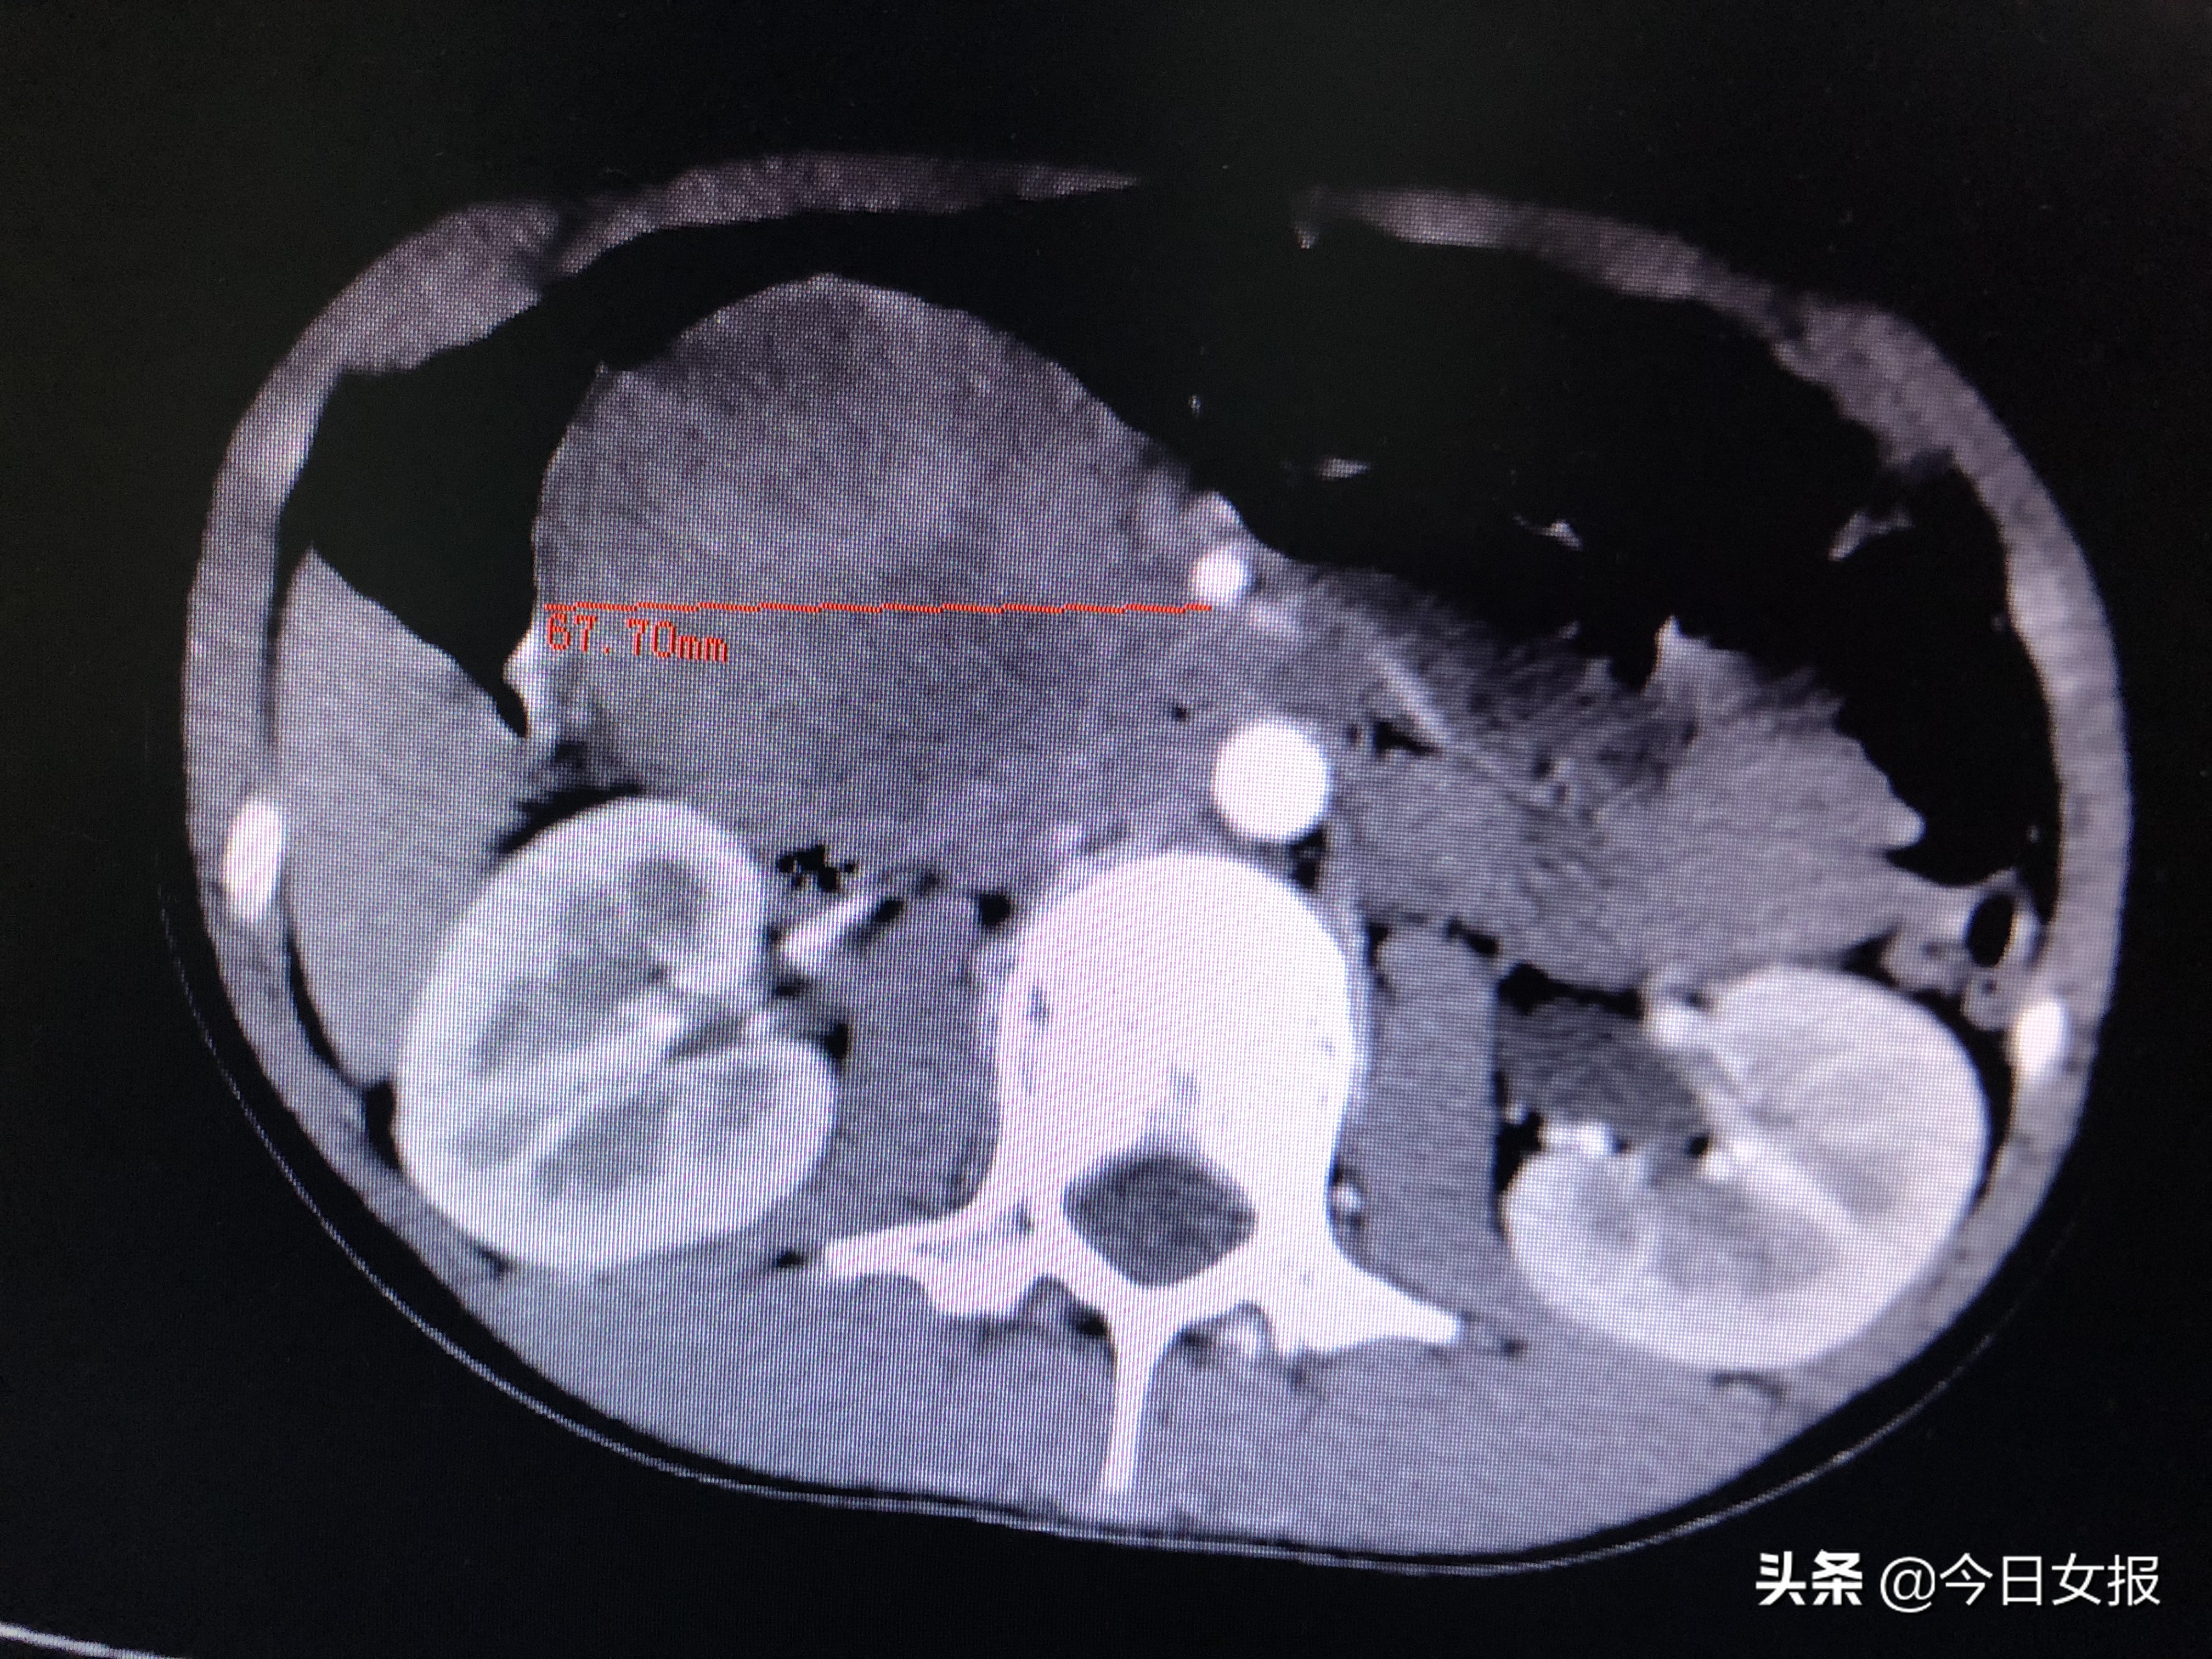

4月17日晚上7时许,在完善相关检查进一步明确病情并排除手术禁忌后,由蒋波、陈梅福、成伟等专家组成的手术团队为婷婷施行急诊全麻下腹腔镜胰十二指肠切除术。术中发现,肿瘤压迫十二指肠、结肠,且出血后粘连严重,腹腔镜下分离难度极大;同时,肿瘤与肠系膜上静脉、肠系膜上动脉、门静脉等重要血管紧邻,一不小心就容易损伤这些大血管,手术风险和难度不言而喻。所幸在专家团队的高超技艺和谨慎操作下,手术于次日凌晨3时许顺利结束,切下的肿瘤达67×61×50mm3,病理检查证实为“胰头实性假乳头状瘤并出血”。